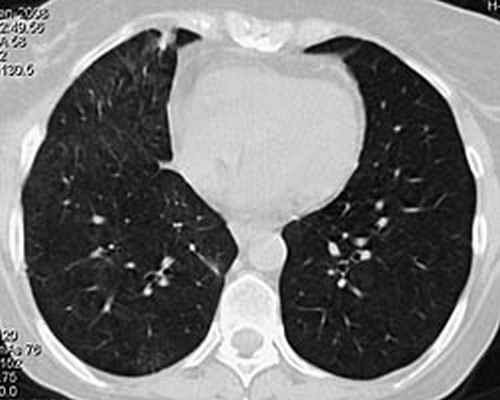

На фоне проводимой пульс-терапии солумедролом и циклофосфаном состояние и самочувствие быстро улучшались: температура тела стойко нормализовалась на 2 день, кровохарканье сохранялось еще 4 суток. В дальнейшем проводилась терапия метипредом 40 мг/сут., 2 недели аугментином 2,0 г/сут., противогрибковая терапия вифендом, (до иммунологического подтверждения диагноза). Клинический анализ крови, мочи от 7.02.08 в пределах нормы. В удовлетворительном состоянии 8.02.08 выписана на амбулаторное лечение. В марте 2008 приступила к работе. При контрольной КТ органов грудной клетки в марте 2008: инфильтративных изменений в легких не выявлено (рис 4). Клинический анализ крови в пределах нормы. Жалоб нет. Начато снижение дозы метипреда по схеме, к терапии добавлен метотрексат 10 мг/нед. с гормонсберегающей целью.

Рис 4. КТ органов грудной клетки 18.03. 2008: в легких изменений нет. Особенностью представленного клинического наблюдения явилось деструктивное поражение легких в дебюте заболевания, являющееся проявлением микроскопического полиангиита лишь в 50% случаев. Адекватное, максимально быстрое начало лечения при столь грозном заболевании позволяет достигать ремиссии более чем у 65% пациентов.